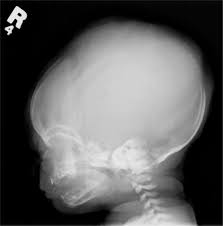

images

aconroa pelazia

این تصویر بیماری ( آکندرو پلاژیا ) رو نشون میده .

بله این بیماریه اکندو پلاژیا است...

برای شروع اول یه چی آسون میذارم..........

حسان جان من اصلا از ژنتیک چیزی نمیدونم و هرچی یادمه از زیست دبیرستانه توی این عکس پسر سمت راست از شکل چشم هاش به نظرم منگلولیسم داره

به احتمال خیلی زیاد اسم بیماری آکندروپلازی هست !

که معمولا والدین سالمن و طی جهش بچه اینطوری میشه

میشه اسم بیماریش رو گذاشت کوتولگی؟بنده خدا جا مونده!!!!!!!!!

استخوان جمجمه رشد نکرده مبتلا به بیماریه سر ابکیه،خودمون تازه کشف کردیم